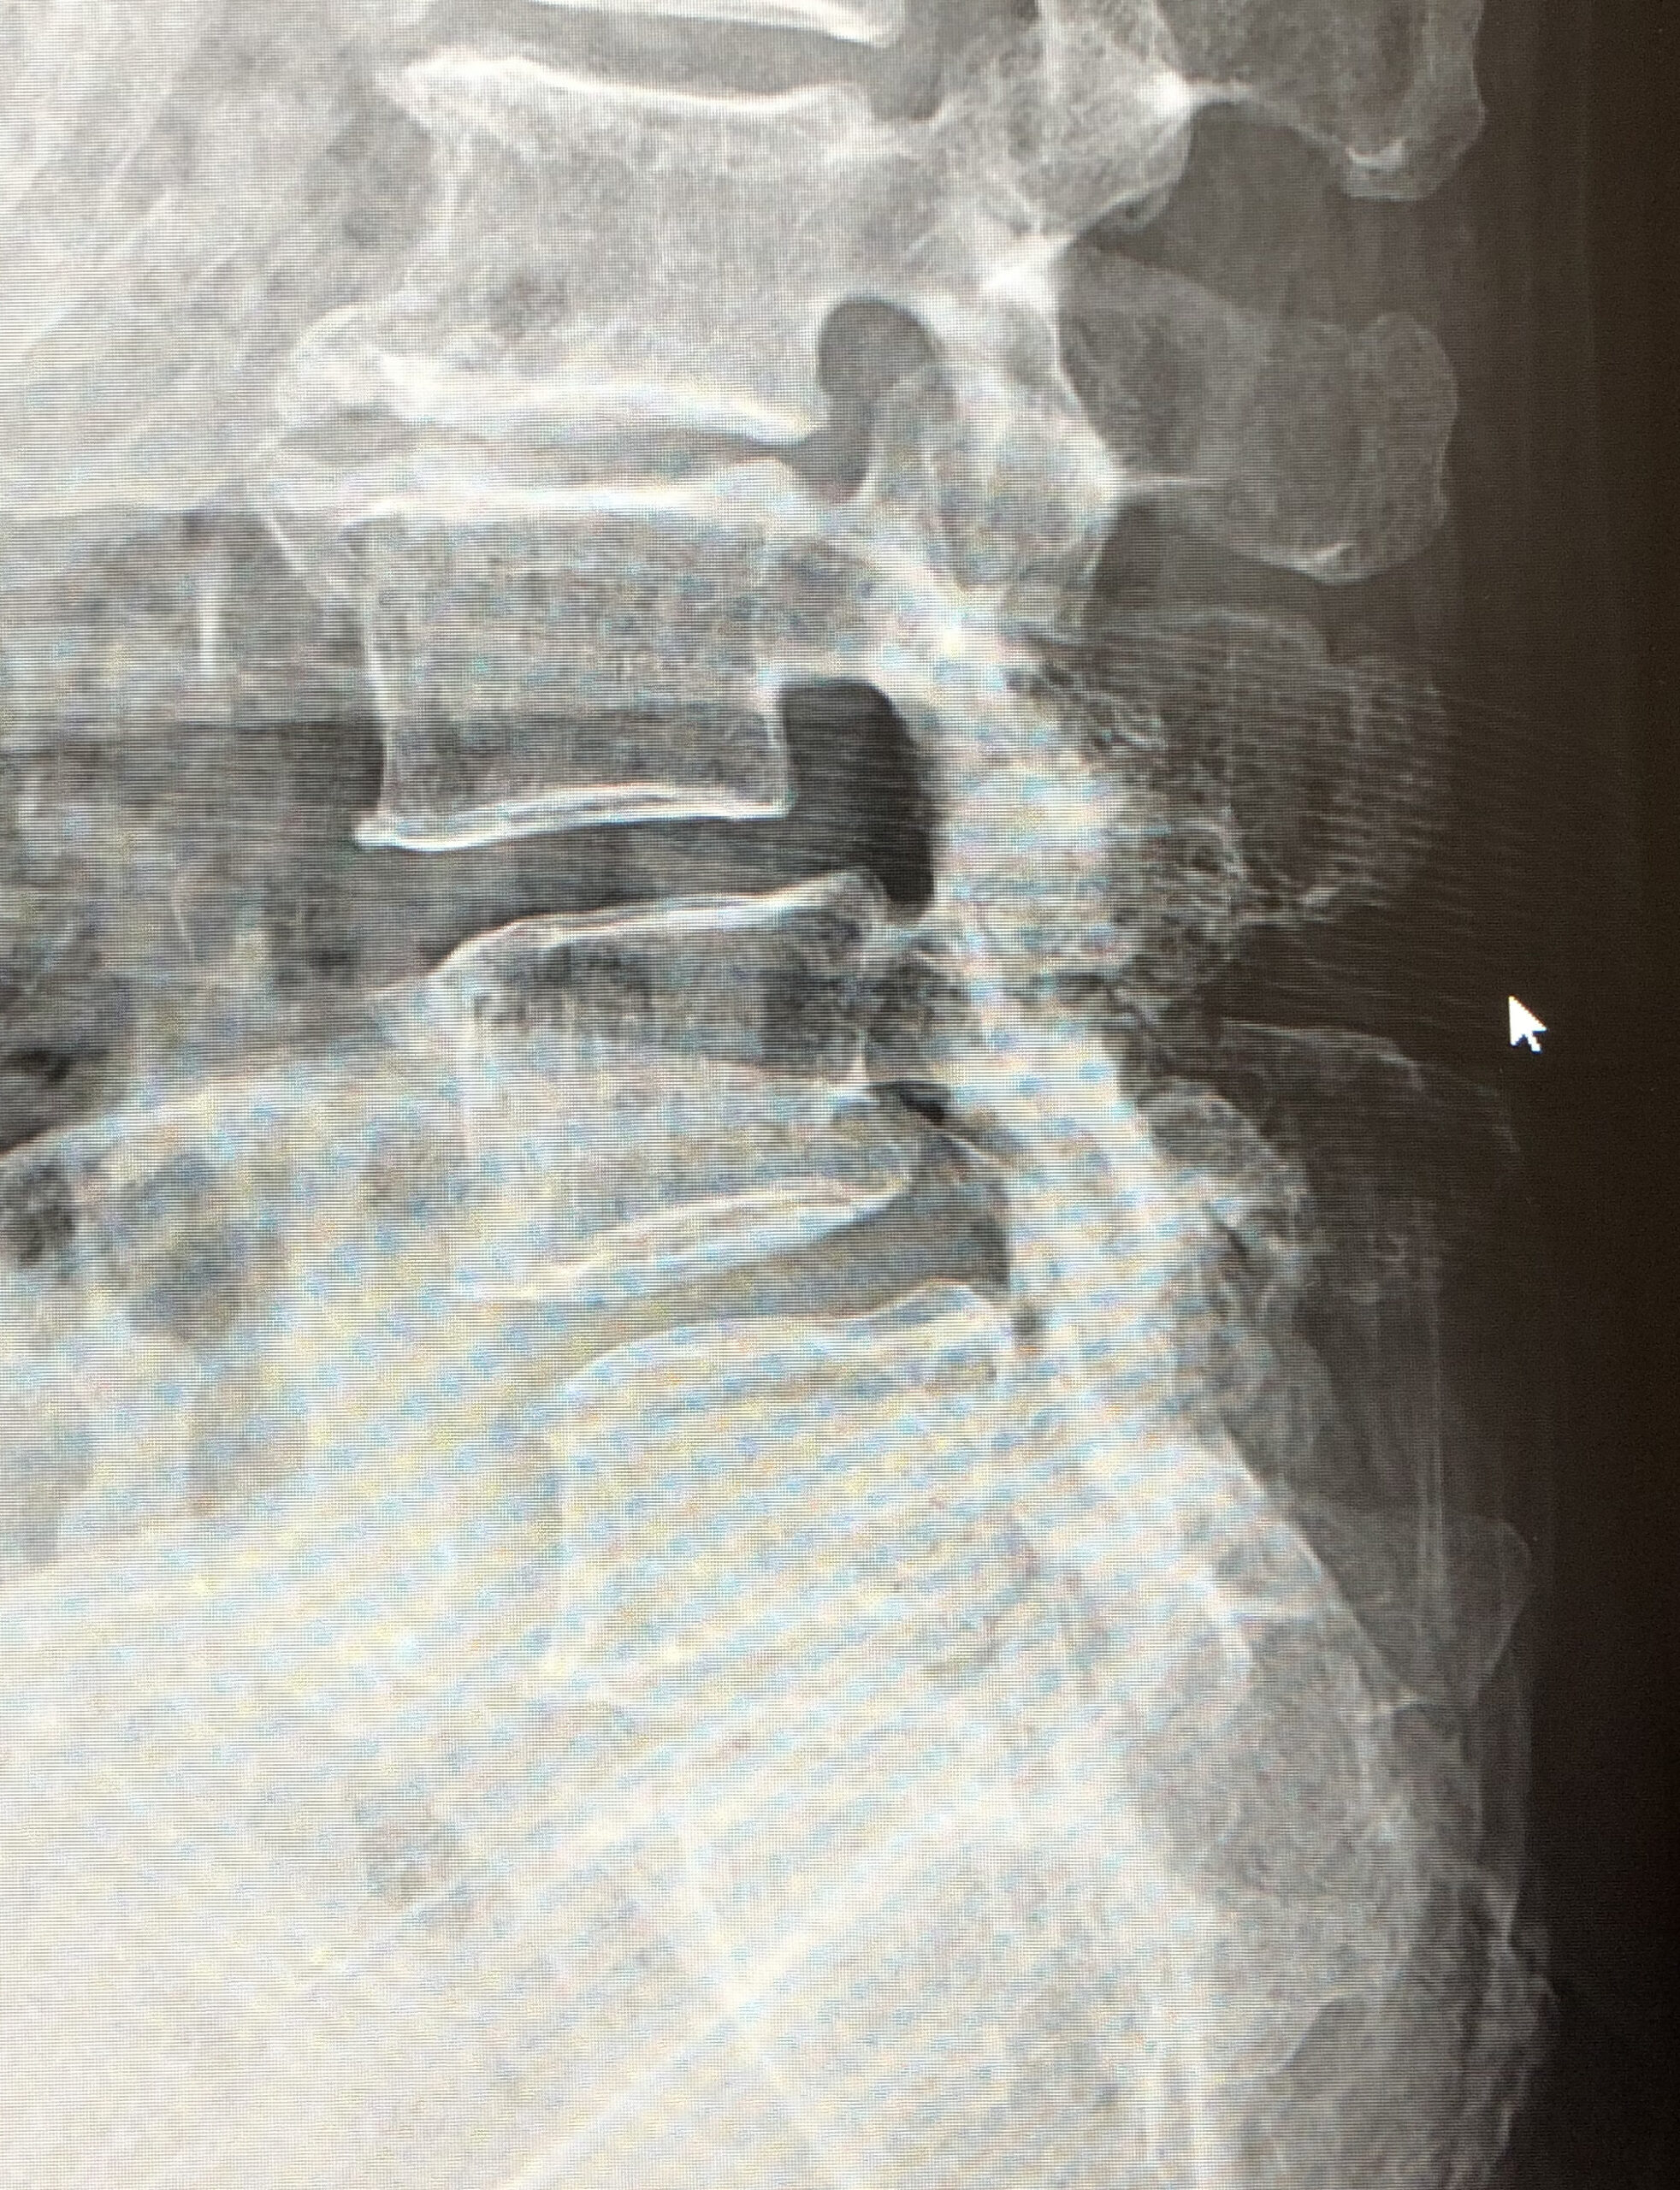

脊椎のすべりにより高度の脊柱管狭窄がある場合に、後方からすべりの矯正や神経の除圧が同時に行える手術です。

| 術前 | 術後 | |

|---|---|---|

| X線 |

|